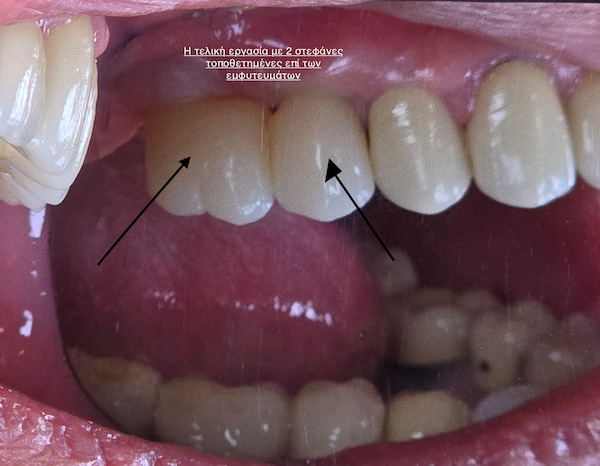

Μετά την πλήρη ενσωμάτωση, τα εμφυτεύματα “αποκαλύπτονται” και τοποθετείται ένας κοχλίας επούλωσης, που βοηθά στη διαμόρφωση των ούλων γύρω από τη μελλοντική στεφάνη.

Μετά από 2–3 εβδομάδες, λαμβάνεται αποτύπωμα και το δείγμα αποστέλλεται στο οδοντοτεχνικό εργαστήριο, όπου κατασκευάζεται η τελική αποκατάσταση.

ΠερισσότεραΤα εμφυτεύματα αποκαθιστώνται προσθετικά είτε με ακίνητες αποκαταστάσεις, είτε με κινητές αποκαταστάσεις.